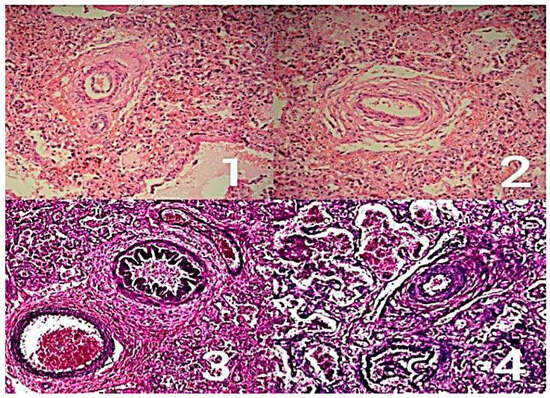

- Romanowicz, H.; Czichos, E.; Zych-Krekora, K.; Krekora, M.; Słodki, M.; Respondek-Liberska, M. Retrospective analysis of prenatal echocardiography findings in cases of congenital heart defects: Comparison with postnatal pulmonary hypertension revealed by lungs histopathology (2010–2015). Prenat. Cardiol. 2015, 5, 12–18. [Google Scholar] [CrossRef][Green Version]